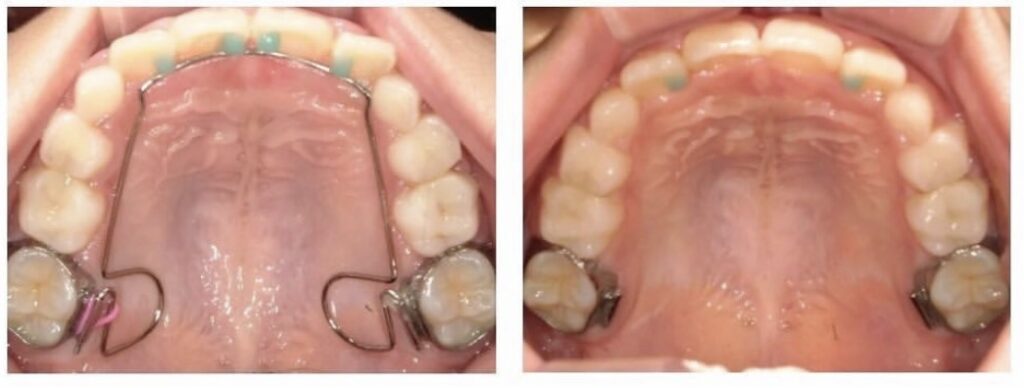

BWSの装着

歯並びも良くなってきていますが、まだアーチは完全なUの字にはなっていません。

そのため舌のお手伝いをしてくれる装置を一時的に入れました。

3ヶ月頃で外すのですが、しっかり前歯が並んできています。

ですがまだ3番目の歯が入る余裕はない状態です。